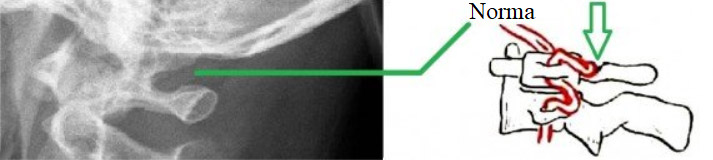

Întâlnită la 12-30% de oameni, această anomalie nu este o maladie, ci de fapt - o variantă anatomică a primei vertebre cervicale (atlasul), produsă din osificarea completă sau incompletă a ligamentului posterior atlanto-occipital peste șantul arterei vertebrale, rezultând în formarea unui foramen arcuat (arc osos suplimentar) care conține artera vertebrală și ramura posterioară a nervului spinal C1, și care poate limita mișcarea (fluxul) arterei vertebrale, provocând sindromul de compresie mecanică a ei.

Un simplu Roentgen al regiunii craniovertebrale, o tomografie computerizată, o angiografie prin rezonanță magnetică, o dopplerografie a vaselor capului și gâtului sau scanarea duplex fac posibilă evidențierea acestei anomalii.